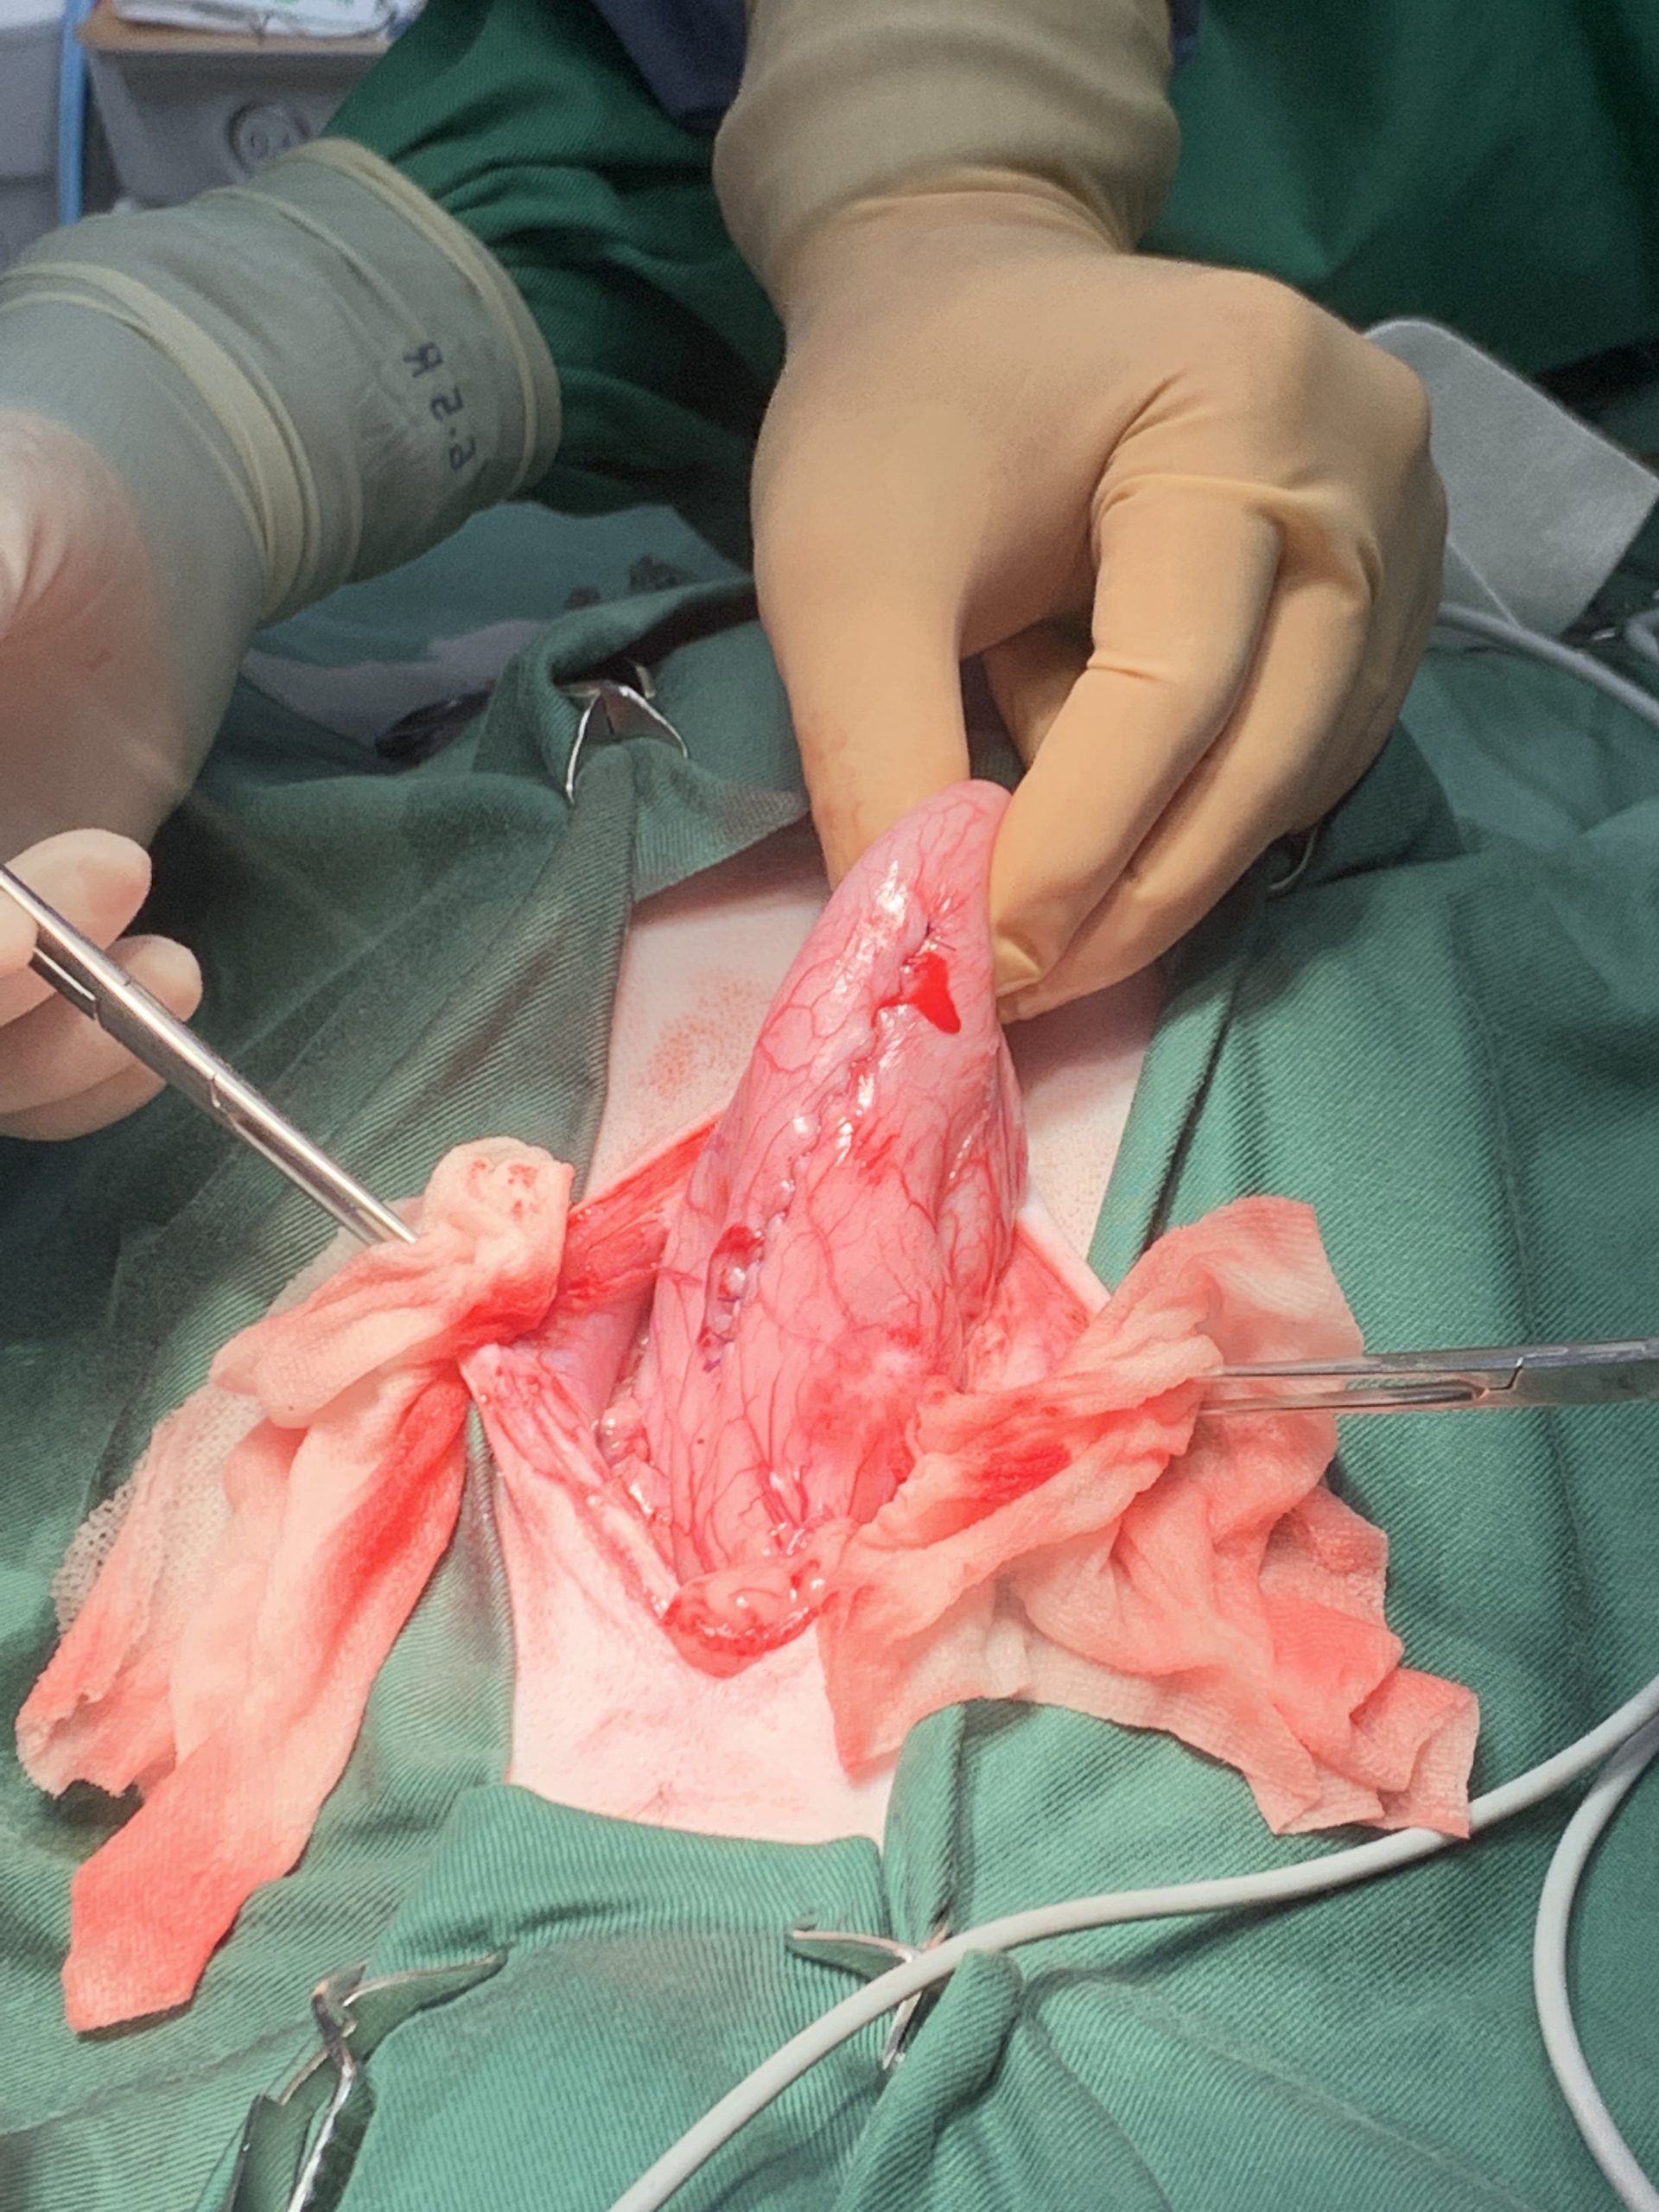

実際の手術の画像がありますので苦手な方はお控えください

手術中の画像になります。助手の方に胃を牽引してもらいながら胃の中の内容物が外に漏れ出ないように慎重に進めていきます。また胃の周囲にはガーゼを敷き詰めこれも胃内容物により腹膜炎などが起こらないように注意しています。

縫合後の胃の状態